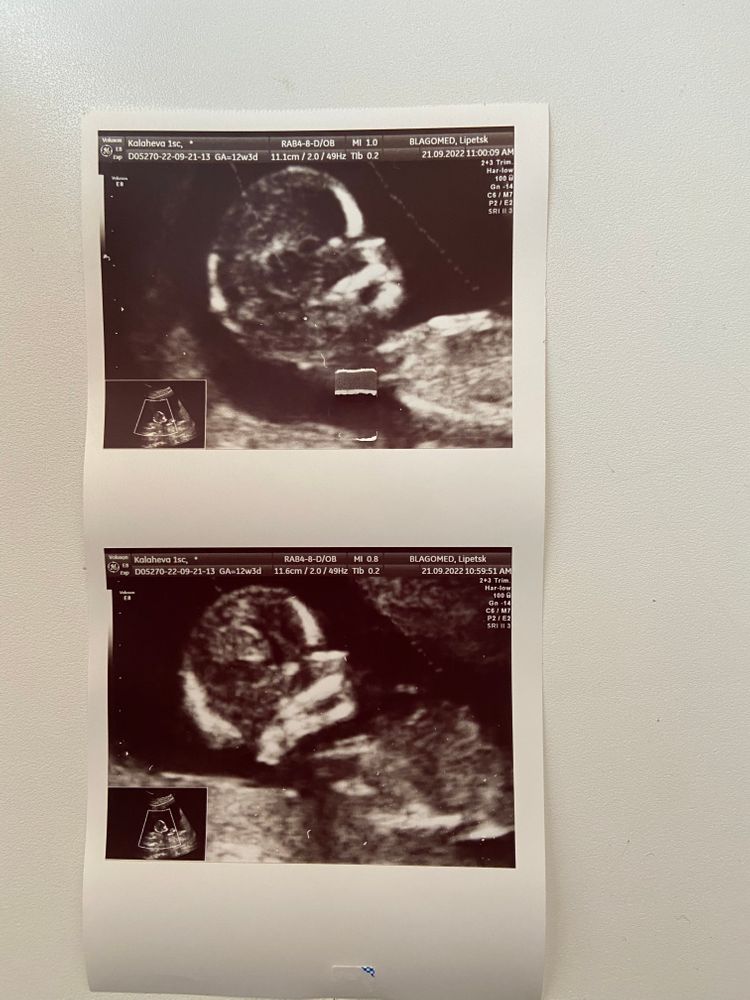

1 скрининг

Сегодня наконец-то прошёл наш первый скрининг! Очень переживала и ждала данное мероприятие.

На узи малышка рассмотрели вдоль и поперёк. Даже разрешили поприсутствовать мужу и разглядеть нашего человечка получше) ребёночек такой активный, вертелся и брыкался то и дело, уже непоседа какой-то 😀

по измерениями вроде все нормально, единственное смущает окружность головы, которая соответствует сроку на неделю позже. Это норма или стоит накрутить уже ? 🤔